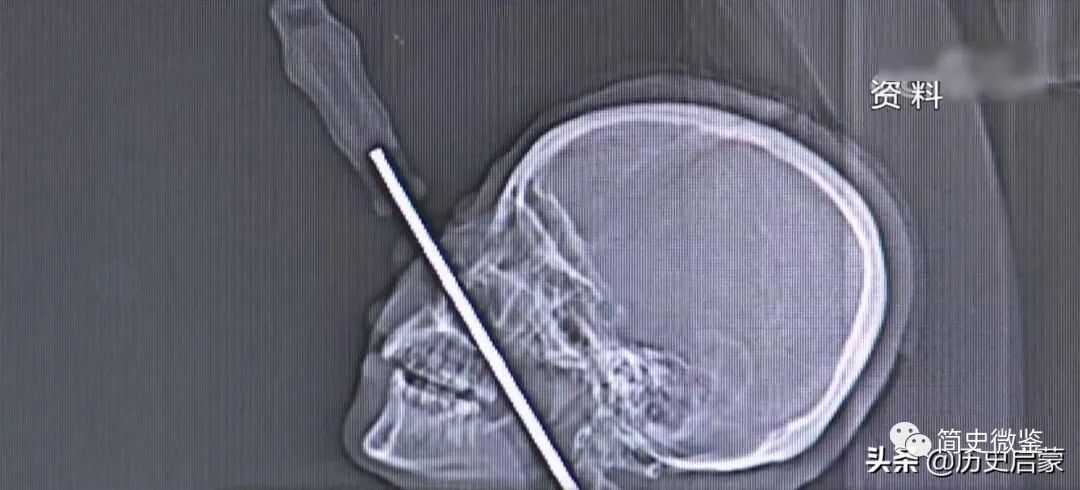

而被送往医院的女子还在死亡线上挣扎,CT检查结果出来后,在场的人都倒吸了一口凉气。

经检查,插进她脸部的螺丝刀部分约有15厘米左右,越过了鼻腔口腔,直达颈椎。